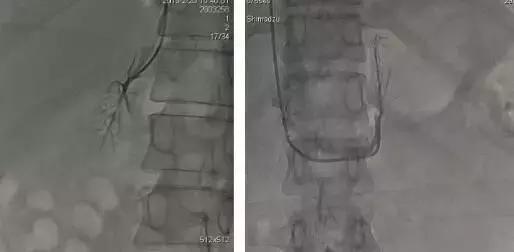

肾上腺静脉显影 肾上腺静脉显影

天津医科大学总医院AVS多学科团队,目前开展经肘正中静脉穿刺AVS项目,主要术者为DSA中心的付殿勋医生。

该技术借鉴中国医学科学院阜外医院经验,成功改良既往经典分侧肾上腺静脉取血技术,术中通过配合不同型号造影导管的精妙使用,一定程度克服右侧肾上腺静脉开口成角过大等解剖因素影响,技术成功率达90%以上。